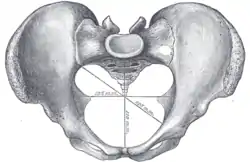

Diameters of pelvic inlet

Right hip bone. External surface.- Pelvic girdle anatomy